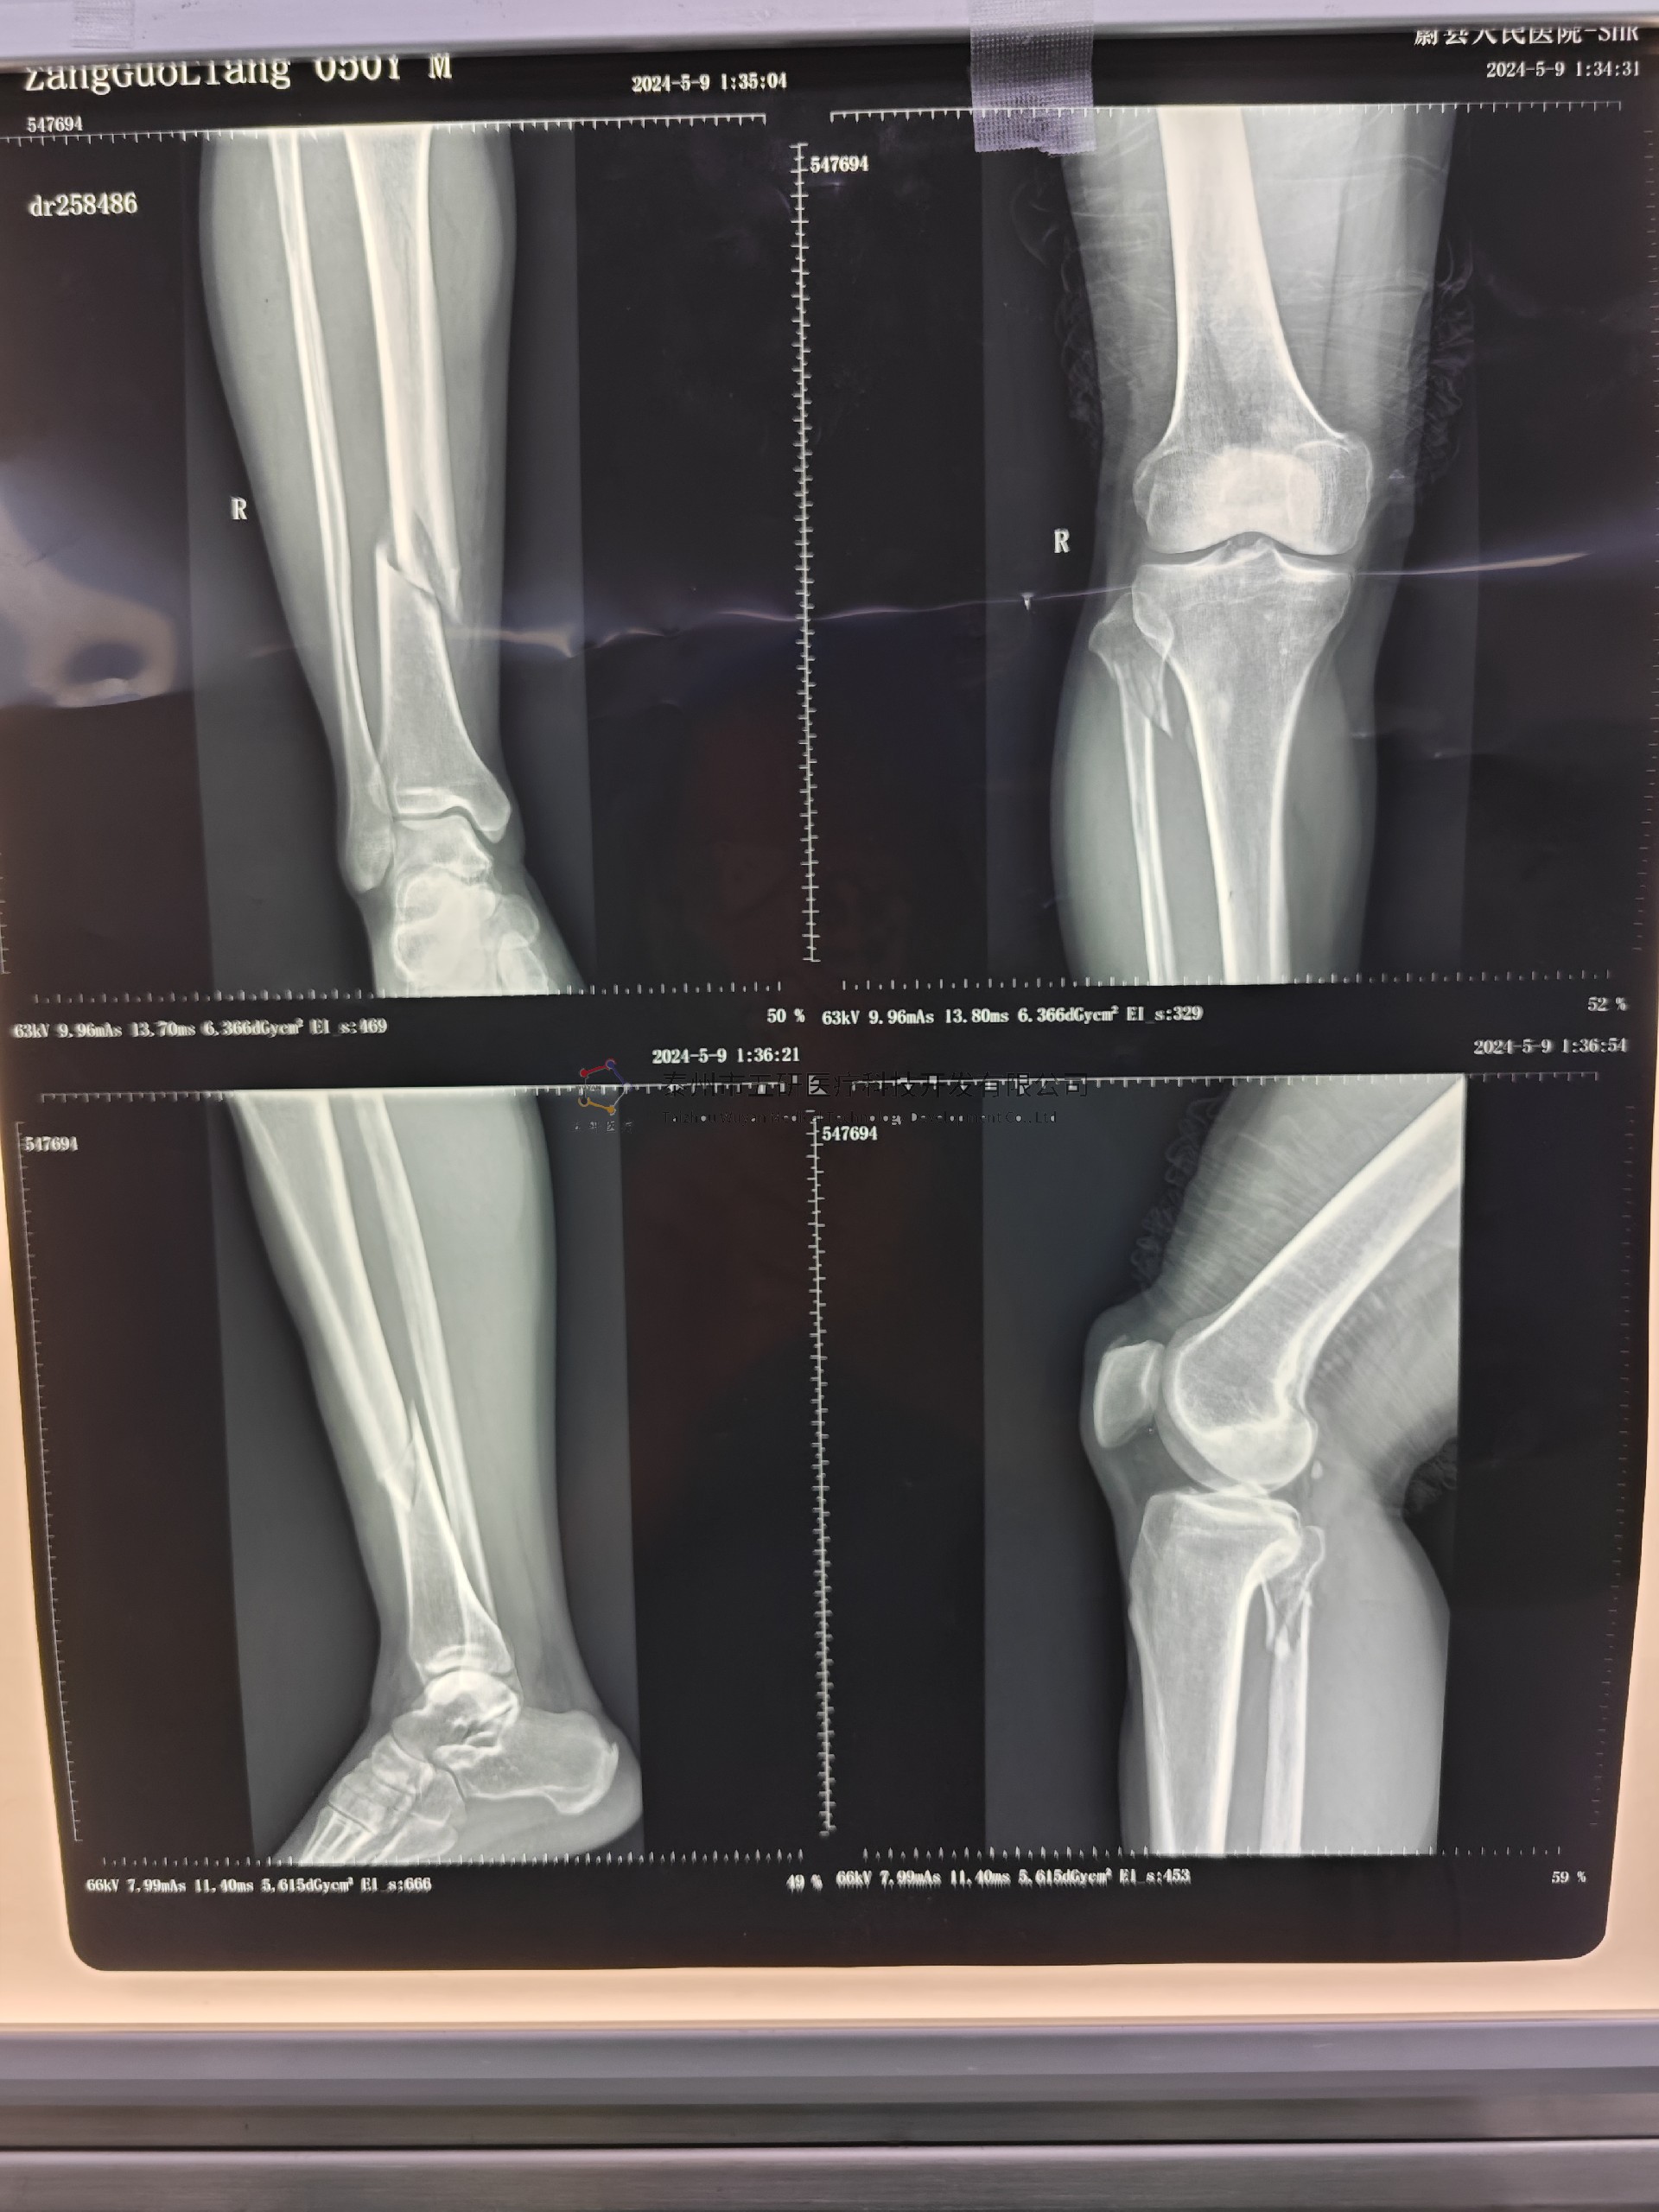

本病例由中國中醫(yī)科學院望京醫(yī)院骨骨綜科提供

術前X片